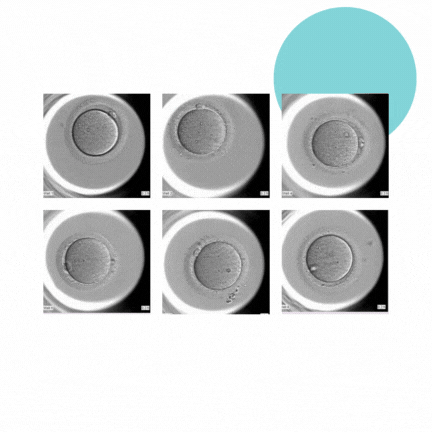

A clinica Primordia mais uma vez mantêm seu pioneirismo em alta tecnologia na Reprodução Assistida. É a primeira clínica do Rio de Janeiro a oferece para seus pacientes a incubadora Time-Lapse. EmbryoScope® Plus, equipamento de última geração que possui sistema de monitoramento contínuo Fornecendo imagens em tempo real do desenvolvimento embrionário, e permitindo avaliar com melhor precisão padrões da evolução dos embriões, 24 horas por dia, sete dias por semana.

- Monitoramento contínuo: A EmbryoScope® Plus é uma incubadora com câmera de time-lapse que tira fotos dos embriões em desenvolvimento em intervalos regulares. Isso permite que os embriologistas monitorem o desenvolvimento do embrião sem ter que retirá-lo da incubadora, o que pode ser estressante para o embrião e aumentar o risco de danos.

- Melhora a seleção do embrião: As imagens capturadas pela EmbryoScope® Plus fornecem informações valiosas sobre a qualidade do embrião, como sua taxa de divisão celular e a uniformidade da célula. Isso ajuda os embriologistas a selecionar os embriões com maior probabilidade de se implantar com sucesso no útero materno.

O sistema Time-lapse é um padrão de atendimento. Sua finalidade é a cultura e avaliação dos embriões, aumentando as porcentagens de sucesso do tratamento de fertilização in vitro, através de uma melhor avaliação desse embrião.

A tecnologia de time-lapse reduz as restrições no tempo de observação e o possível estresse dos embriões durante a cultura e a avaliação. A análise dos embriões se torna mais objetiva e precisa, sem contato humano.